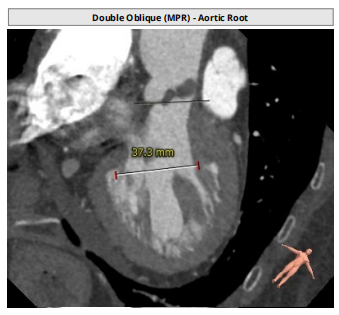

近日,珠海市人民医院心血管内科姜小飞主任带领瓣膜介入团队,在超声科张恒主任团队、麻醉科刘贵德主任团队以及影像科等兄弟科室全力配合下,成功为一位主动脉瓣重度狭窄合并轻度返流的患者完成经导管主动脉瓣置换术(TAVR)。该病例极具挑战性,病人整体结构小,瓣环16.9mm,左室流出道16.7mm,窦管结合部23.9mm,升主动脉31.4mm。在姜小飞主任团队前期充足的准备,通过术前评估,制定手术策略和预案,充分对比目前可以使用的瓣膜系统,最后应用VenusA-Plus挑战成功了三叶式“4小”高难度TAVR病例。

瓣环:16.9mm;左室流出道:16.7mm

患者为三叶瓣,左右、右无疑似粘连,瓣叶明显增厚,轻度钙化。右冠高度10.9mm,左冠高度9.5mm,冠脉高度均较低。法式窦小,心脏角度不大,左室大小可,升主动脉未见明显增宽,病人整体结构小,瓣环仅有16.9mm,左室流出道16.7mm,窦管结合部23.9mm,升主动脉31.4mm。选择右股作为主入路。